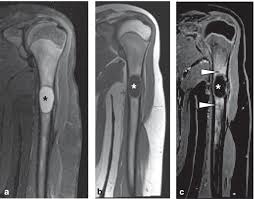

В режиме Т1 определяется гипоинтенсивный сигнал от образования в пределах кости, соответствующий жидкости или серозному содержимому.

В режиме Т2 визуализируется гиперинтенсивный сигнал от полости с однородным или неоднородным содержимым, при наличии перегородок или взвеси.

В режиме с подавлением сигнала от жира подчёркиваются границы между кистозной капсулой и окружающим губчатым веществом, включая возможный отёк костного мозга.

В режиме с контрастированием, как правило, не отмечается накопления контрастного вещества в центральной части, однако усиление может наблюдаться по периферии при реактивных изменениях.

На многоплоскостной визуализации определяется форма, протяжённость, локализация и степень утончения кортикального слоя в зоне кистозного процесса.